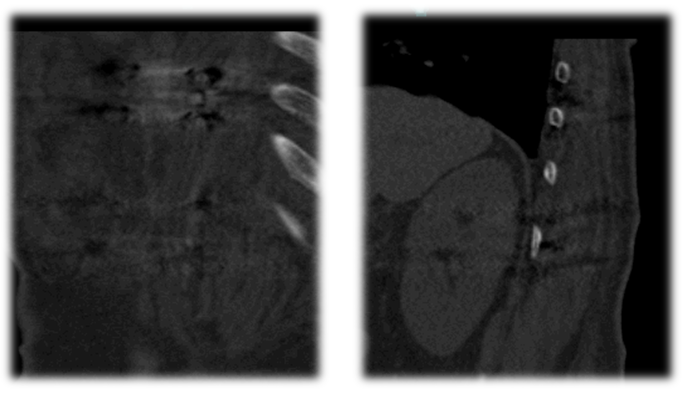

术后CT

•      术后3月CT